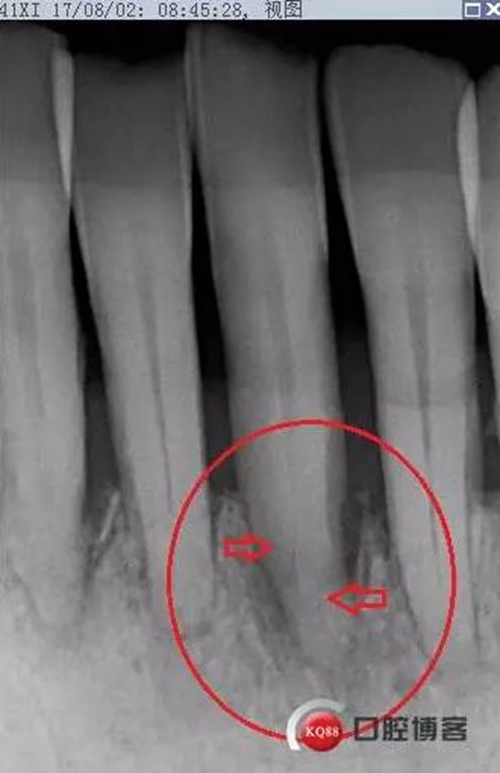

處理:上橡皮障,31開髓,測工作長度17mm,含氯沖洗液沖洗,機擴至04錐度30#,超聲蕩洗,一次性根充。33-43牙齒鄰接處super bond粘結(jié)固位,行松牙固定。調(diào)合。拍根充術后片,未達根尖,懷疑遺漏根管,去除根充物后,繼續(xù)探查根管,找到舌側(cè)根管,測長度20mm,時間原因,未行擴根,氫氧化鈣暫封。

圖省事,沒有拍術中試尖片,導致術后重新去除根充物,再次探查,耽誤時間。

想當然的認為31單管,忽略了尚有5-10%概率的雙根管情況。

事后再次查看術前片,可以看到兩個根管影像,忽略了。